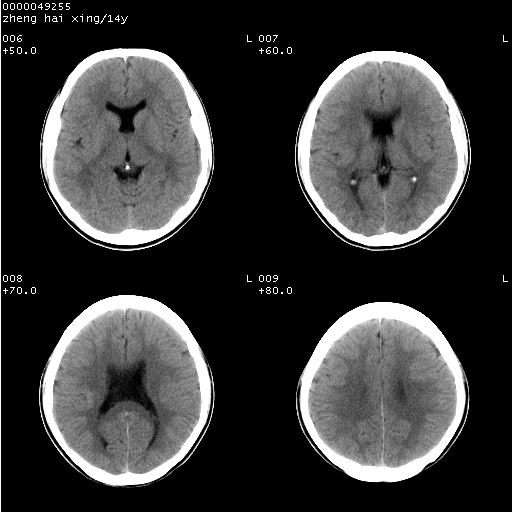

患儿 男,14岁。头部外伤1小时。pe:发育正常,营养良好,生命体征稳定,未见明显阳性体征。

临床诊断:ⅰ级脑外伤。

颅脑ct轴位平扫(层厚、层距均为10mm),图像如下:

(患儿平素健康,双眼视力正常,无神经系统及内分泌系统症状及体征)

双侧侧脑室之间无透明隔,双侧额角前方变扁,交角变钝。支持透明隔缺如!

透明隔缺如可为先天性缺如,亦可继发于因脑积水,脑室内压力增高,使其变薄,以至不能显示。一般无临床意义,但可并发于其他畸形或作为隔—视综合征的组成部分。

(隔—视发育不良综合征包括:1)原发性视神经发育不良,2)透明隔缺如,3)垂体功能不全,特别是生长激素不足或缺乏)